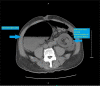

Intussusception is the telescoping of proximal loop of the bowel within distal loop resulting in obliteration of the lumen. Although it frequently occurs with the most common cause of intestinal obstruction in children, it is a rare phenomenon and an uncommon cause of acute intestinal obstruction in adults. Unlike pediatric intussusception, where the cause is idiopathic, adult intussusception is associated with underlying pathology as a lead point. The underlying pathology usually is malignant, but the prognosis is better when there is a benign lead point. The benign lead point intussusceptions are rare and are treated with reduction when there are no signs of ischemia. When there is ischemia or when reduction is not feasible, they are treated with surgical resection. In this report, we describe a rare case of an adult intussusception from a large colonic lipoma in a 79-year-old male, treated successfully with surgical resection.